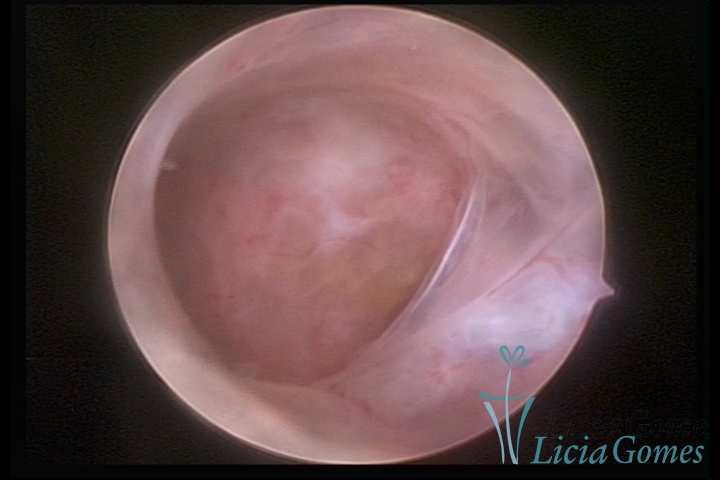

FIBROUS SYNECHIA

Uterine synechiae are scars (adherence) between the surface of the uterine walls, which may occur after the surgical procedure, uterine curettage, or after an inflammatory process in the uterine cavity (endometritis), which may lead to menstrual changes, infertility and obstetric complication such as abortion and premature birth.

SINÉQUIA TIPO MUCOSA